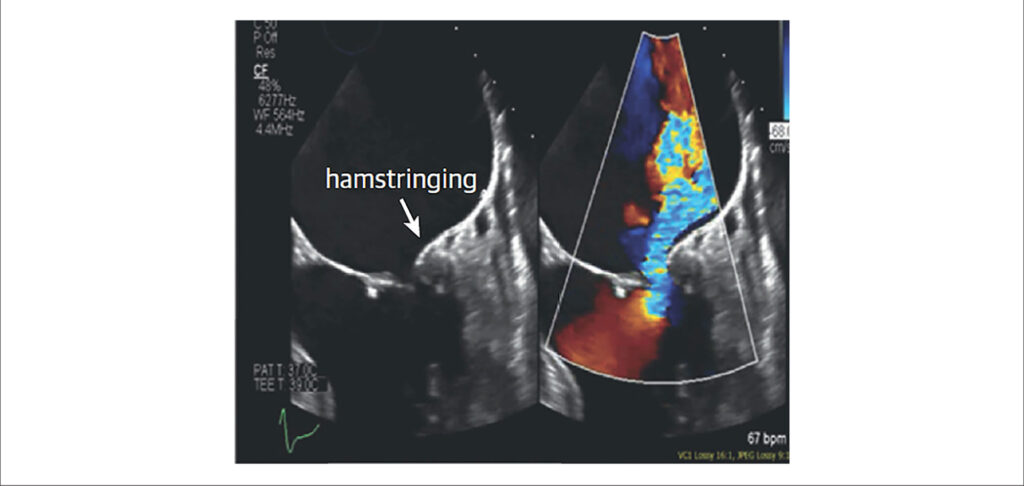

Atrial Functional Mitral Regurgitation

Secondary mitral insufficiency (MI) in the setting of ventricular disease has always been a topic at conferences and has achieved extensive pathophysiological knowledge over the years. More recently, with the increasing incidence of atrial fibrillation (AF) and heart failure with preserved ejection fraction (HFpEF), a new phenotype that had been little discussed has come to light: atrial functional mitral regurgitation. In this entity, special attention should be addressed to the left atrium and the mitral annulus because, in early stages, they present normal left ventricular dimensions and function.